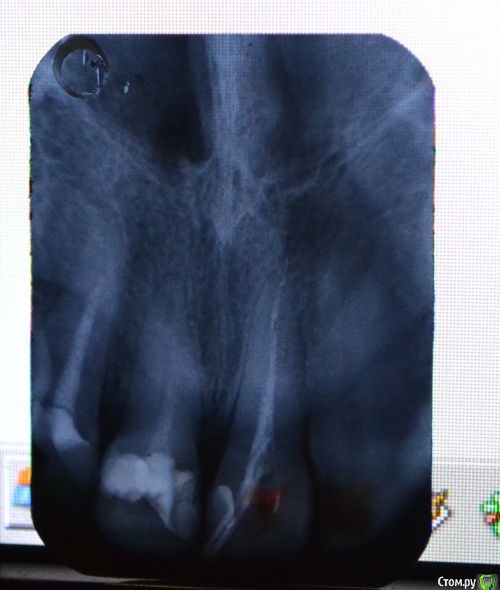

Llllll Опубликовано 28 июля, 2015 Автор Поделиться Опубликовано 28 июля, 2015 Перефотографировала, но не знаю какой снимок лучше, поэтому скинула все которые вышли) В среду канал сразу после этого рентгена запломбировали, к субботе начал очень сильно болеть, терпела, сегодня пошла на прием, открыли канал, но не скажу что стало лучше, может немножко. Боли пульсирующие, около носа, где верхушка зуба. Врач сказала что не знает что дальше делать( И почему оно болит( Ссылка на комментарий

Zlata-doctor Опубликовано 29 июля, 2015 Поделиться Опубликовано 29 июля, 2015 если вы не хотите потерять этот зуб ( а также и два соседних , которые тоже нуждаются в лечении), советую вам найти стоматолога, использующего современные протоколы эндодонтического лечения. Ни один из трех представленных на этих ужасных снимках зубов не пролечен как следует. Линкомицин, гидрокортизон, фонофорез итд -бегите оттуда. Извините за резкий тон, я Вам очень сочувствую. 1 Ссылка на комментарий

St. Опубликовано 11 августа, 2015 Поделиться Опубликовано 11 августа, 2015 По снимку все три зуба нуждаются в качественном лечении. Причем вполне возможно, что какие-то ощущения дает ещё соседний центральный зуб. Кусочка инструмента не увидела.Я понимаю, что найти хорошего стоматолога совсем не просто. Как минимум имейте ввиду, что оставлять зуб открытым - это плохо, колоть в десну антибиотики и гормоны, и выводить много-много чего-то там за пределы зуба - тоже не очень. 2 Ссылка на комментарий

Гарриевич Опубликовано 11 августа, 2015 Поделиться Опубликовано 11 августа, 2015 на этом снимке нет выраженных признаков периодонтита, но это не значит что его нет Ссылка на комментарий